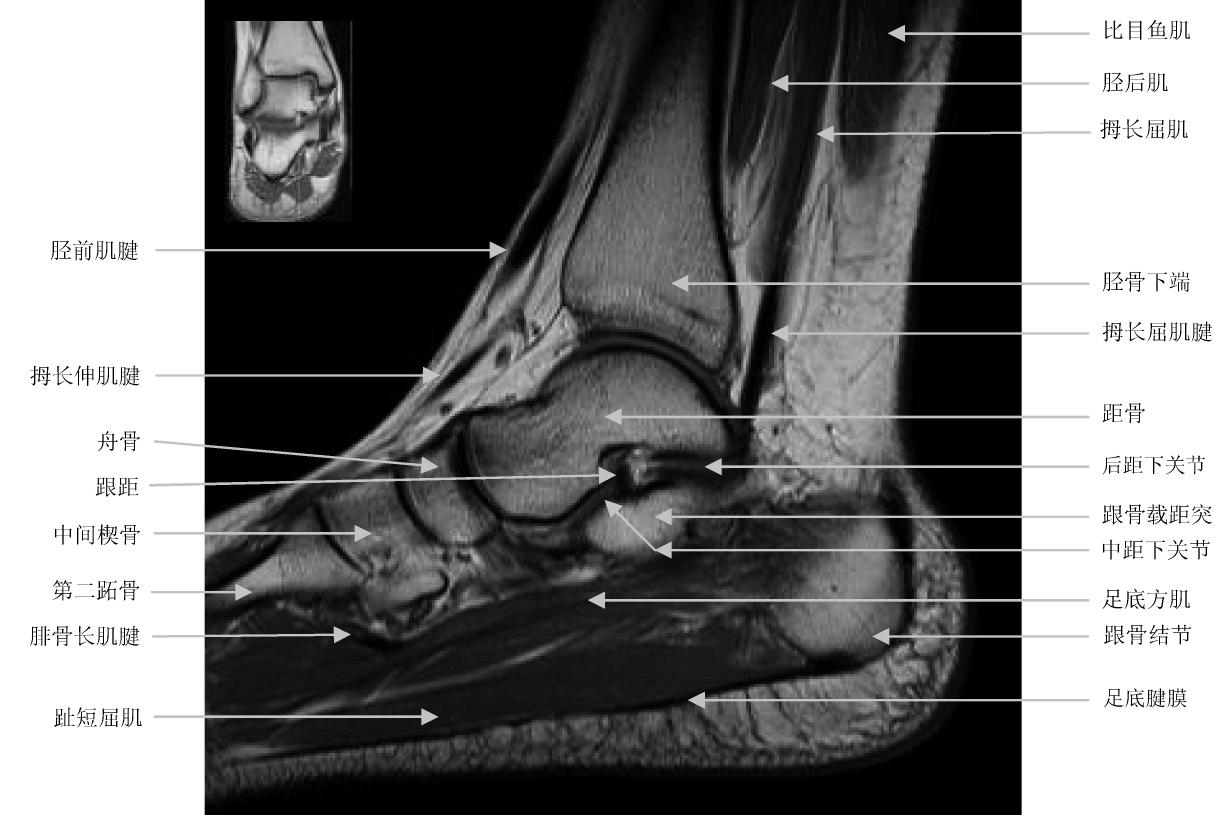

3、核磁共振检查:如下图,韧带、肌肉、肌腱这种软组织只有核磁才能够看清楚,X线及CT主要是用来观察骨性结构,也就是骨头的形态。如果在X线或者CT检查明确无骨性结构的损伤,而脚踝又很肿,怀疑软组织损伤,我们就必须做核磁共振的检查,只是核磁共振检查要比X线及CT检查麻烦一点。